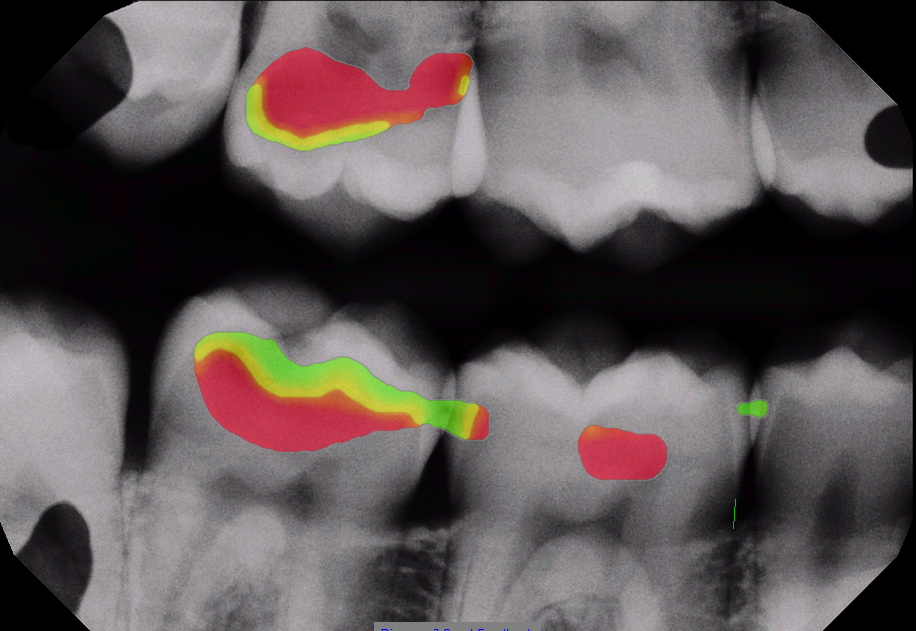

Improve patient education with AI-driven caries detection. Dentists who use Sugarbot benefit from consistent, real-time x-ray analysis.

Sugarbot has received FDA clearance.

Original bitewing With AI overlay

After

Green/yellow/red color display has not received FDA clearance.